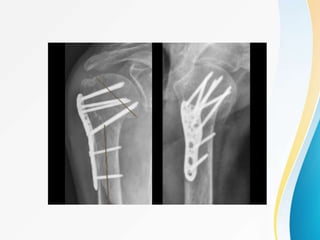

FIXATION OF PHF USING PHILOS(3 PART

AND 4 PART)

-Principles of fixation

-Approaches

-Exposures

-Surgical steps

-Intraop image intensifier(c-arm)

4-PART MARKED DISPLACEMENT, VARUS

MALALIGNMENT , FRACTURE DISLOCATION :

4 STEPS

• Incision through deltopectoral approach

• Reduction and preliminary fixation

• Plate fixation

• Rotator cuff tendon suturing to the plate .